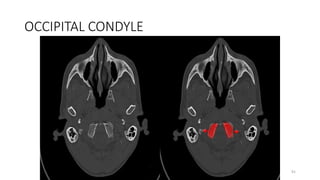

OCCIPITAL CONDYLE

82

91